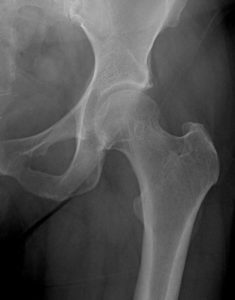

Bone surfaces at joints (such as the hip, knee, or shoulder) are covered by a smooth tissue called cartilage which allows the surfaces to move against each other while providing protection to the bone ends. Arthritis (also called degenerative joint disease) is a condition where this cartilage wears away and changes begin taking place within the joint (figure 1). As cartilage degeneration occurs, pain can develop which can be severe and functional limitations can result.

Note preservation of joint space and congruent hip.